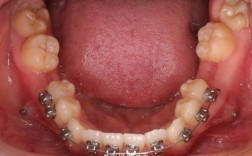

口腔卫生维护难度加大:固定矫治器(如托槽、弓丝)本身易存留食物残渣,提前复诊意味着更频繁的器械接触(如去除弓丝清洁、重新粘接托槽),可能破坏已建立的口腔卫生习惯,若患者未做好清洁,易引发龋齿(尤其是托槽周围)、牙龈炎,严重时导致牙周炎,影响牙齿长期稳定性。

矫治器并发症风险上升:提前复诊时,医生可能因“无异常可调”而进行不必要的操作,如调整原本正常的弓丝弧度、更换未到期的橡皮圈,反而导致托槽脱落、弓丝变形等并发症,据统计,正畸患者中因“非必要调整”导致的托槽脱落率增加15%-20%,需额外时间修复,中断治疗进程。